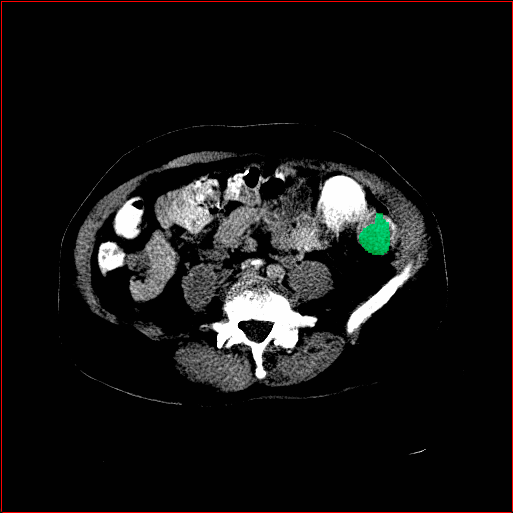

Figure 5 shows qualitative results for MAISI-v2 Controlnet on 5 types of tumors.

Lung Tumor

0.75×0.75×0.60.75\times 0.75\times 0.6

mm

512×512×512512\times 512\times 512

Liver Tumor

0.75×0.75×0.50.75\times 0.75\times 0.5

512×512×768512\times 512\times 768

Panc. Tumor

1×1×11\times 1\times 1

Colon Tumor

0.75×0.75×1.50.75\times 0.75\times 1.5

512×512×256512\times 512\times 256

Bone-Les

1×1×1.31\times 1\times 1.3

512×512×384512\times 512\times 384

Figure 5: MAISI-v2 segmentation-guided results for five types of tumors. We show results for different voxel spacing and volume size to demonstrate the flexibility of MAISI-v2. Different Hounsfield Unit window is used to better show the contrast between tumor and normal tissues.